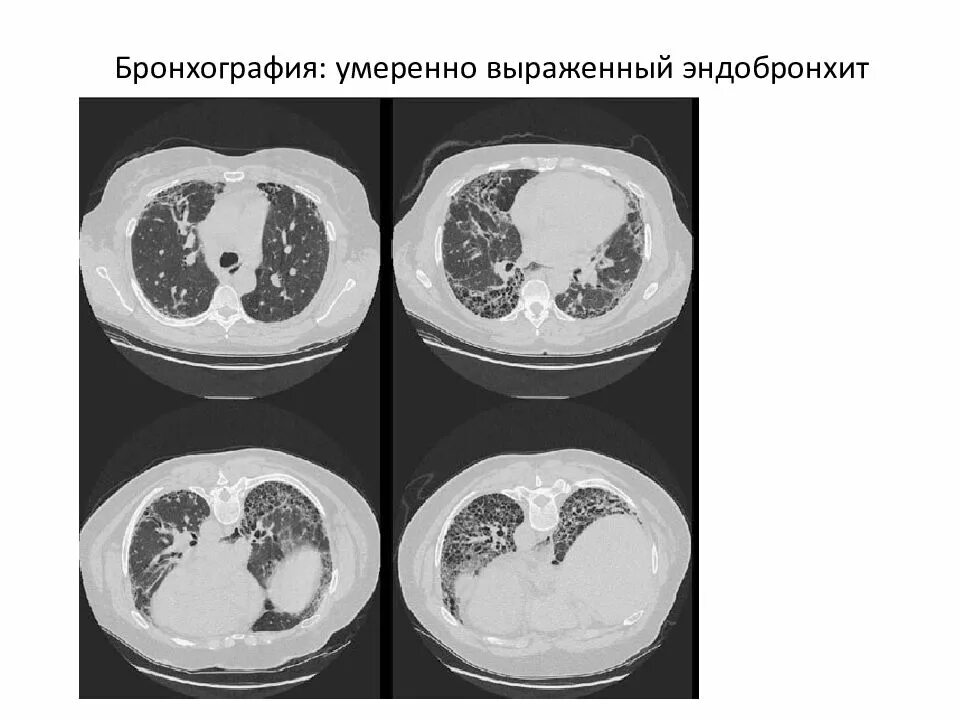

Диффузный эндобронхит